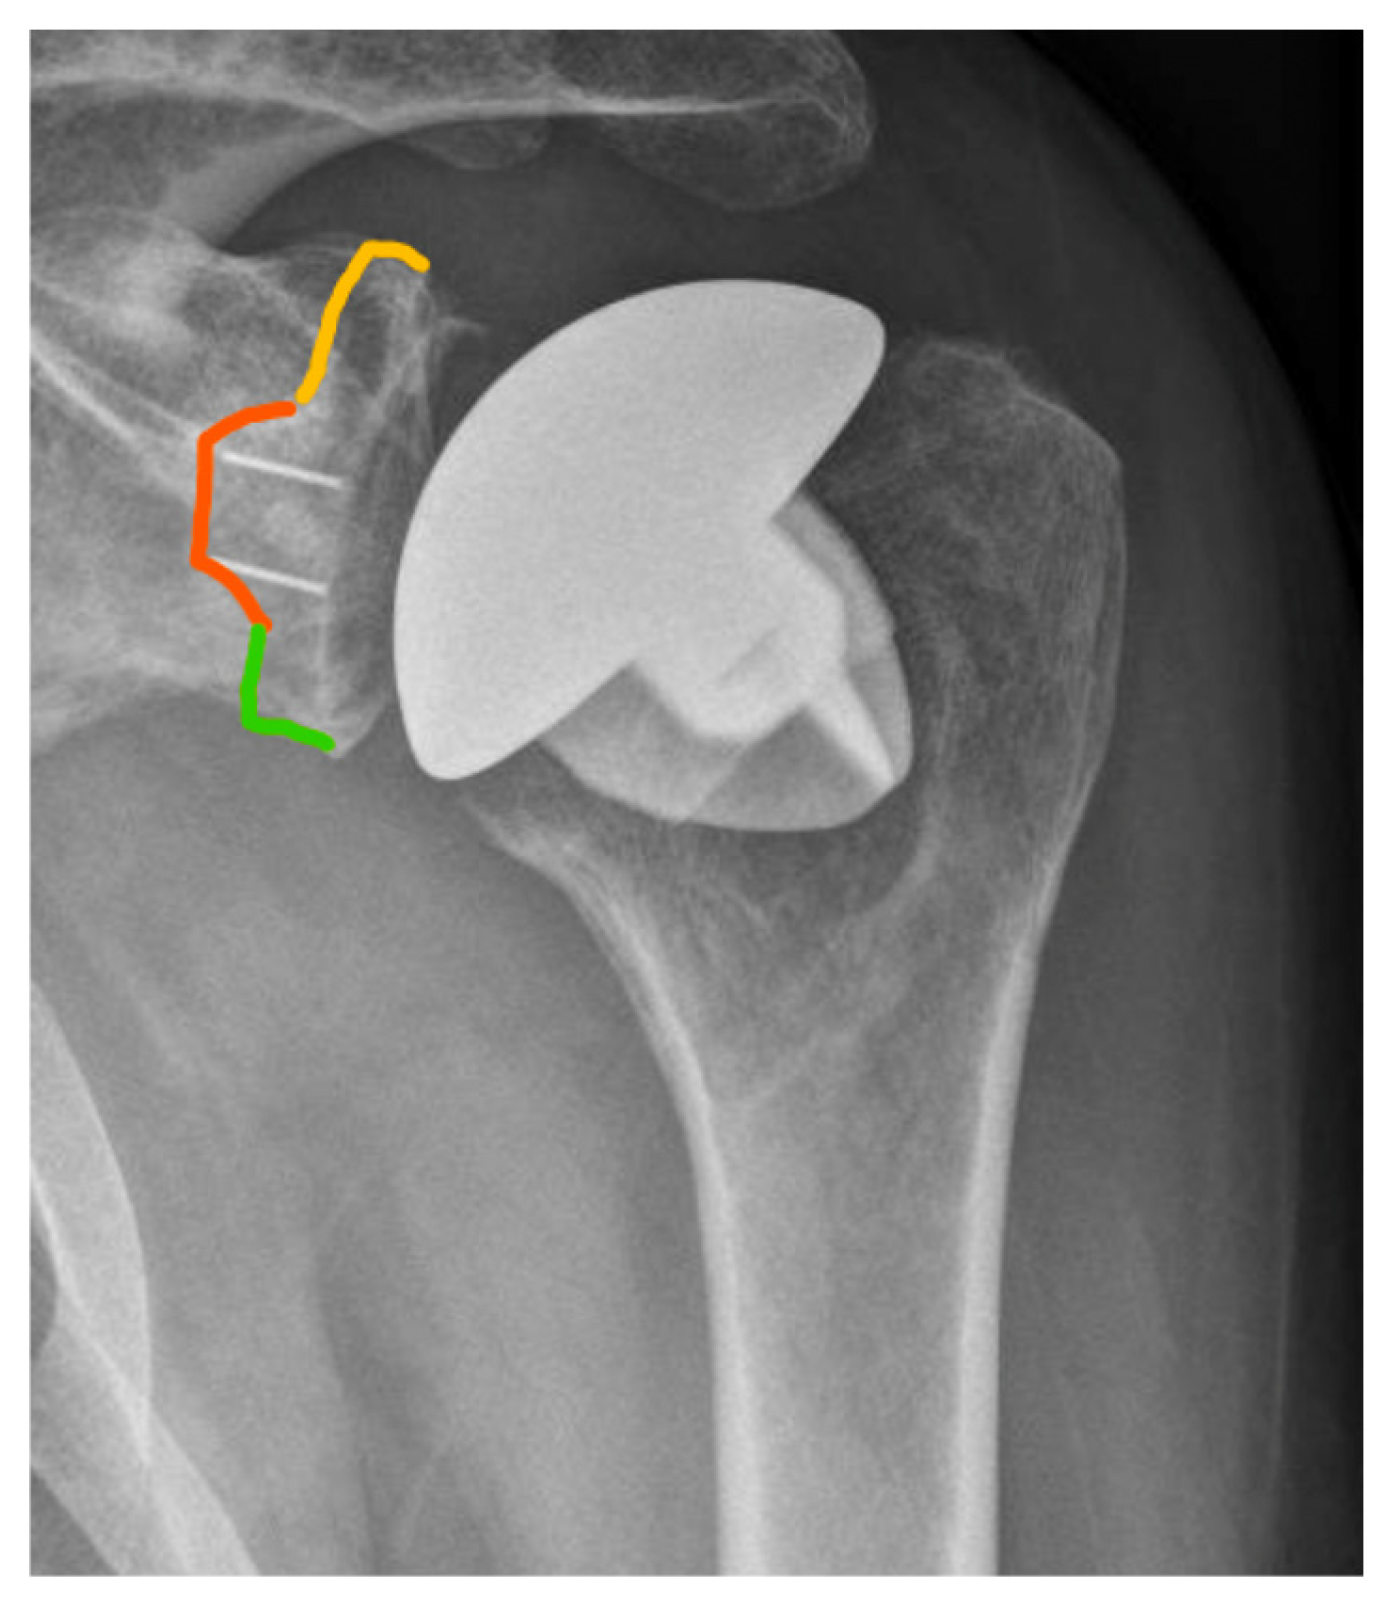

In the present study, only radiolucent lines >2 mm at the cement–bone interface of the glenoid component were defined as gRLL and included in the analysis, in accordance with established radiographic thresholds [6]. Thin radiolucent lines ≤2 mm without evidence of component migration are frequently observed in clinical practice but were not classified as gRLL in this study. These minor changes have been shown to persist over time without leading to clinical symptoms or implant loosening [3]. For standardized localization, gRLL at the cement–bone interface of the glenoid component were classified according to the system by Streck et al. [6]. This divides the glenoid face into three anatomical thirds (superior, medial, inferior) based on the visible distribution of gRLL on standard AP radiographs (Figure 3). The extent of gRLL was quantified by counting the number of affected zones. Patients were subsequently classified according to the extent of gRLL, with extensive gRLL defined as involvement of 3 zones. GSC was defined as migration of the glenoid component within the bone relative to its initial postoperative position. This was determined through comparative analysis of standardized true AP radiographs taken immediately postoperatively and at the final follow-up (Figure 4).

Figure 4. Anteroposterior (AP) radiographs illustrating glenoid component subsidence (gSC). (A): Immediate postoperative implant positioning. The orange circle highlights the base of the coracoid process, and the green spacing measurement indicates the distance to the humeral component. (B): Final follow-up x-ray showing vertical migration of the gSC, with a reduced distance between the coracoid process and the humeral component.